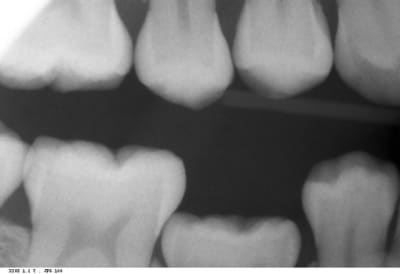

Voici les radios...

vous pouvez remarquer qu'il y a aussi un diasystème entre 34 et 75 ...

85 ss2eyj - Eugenol

85 2 ogqlho - Eugenol

Mais au vu de tes radios, on voit bien que la face distale est clairement en dessous du point de contact de tes 6.